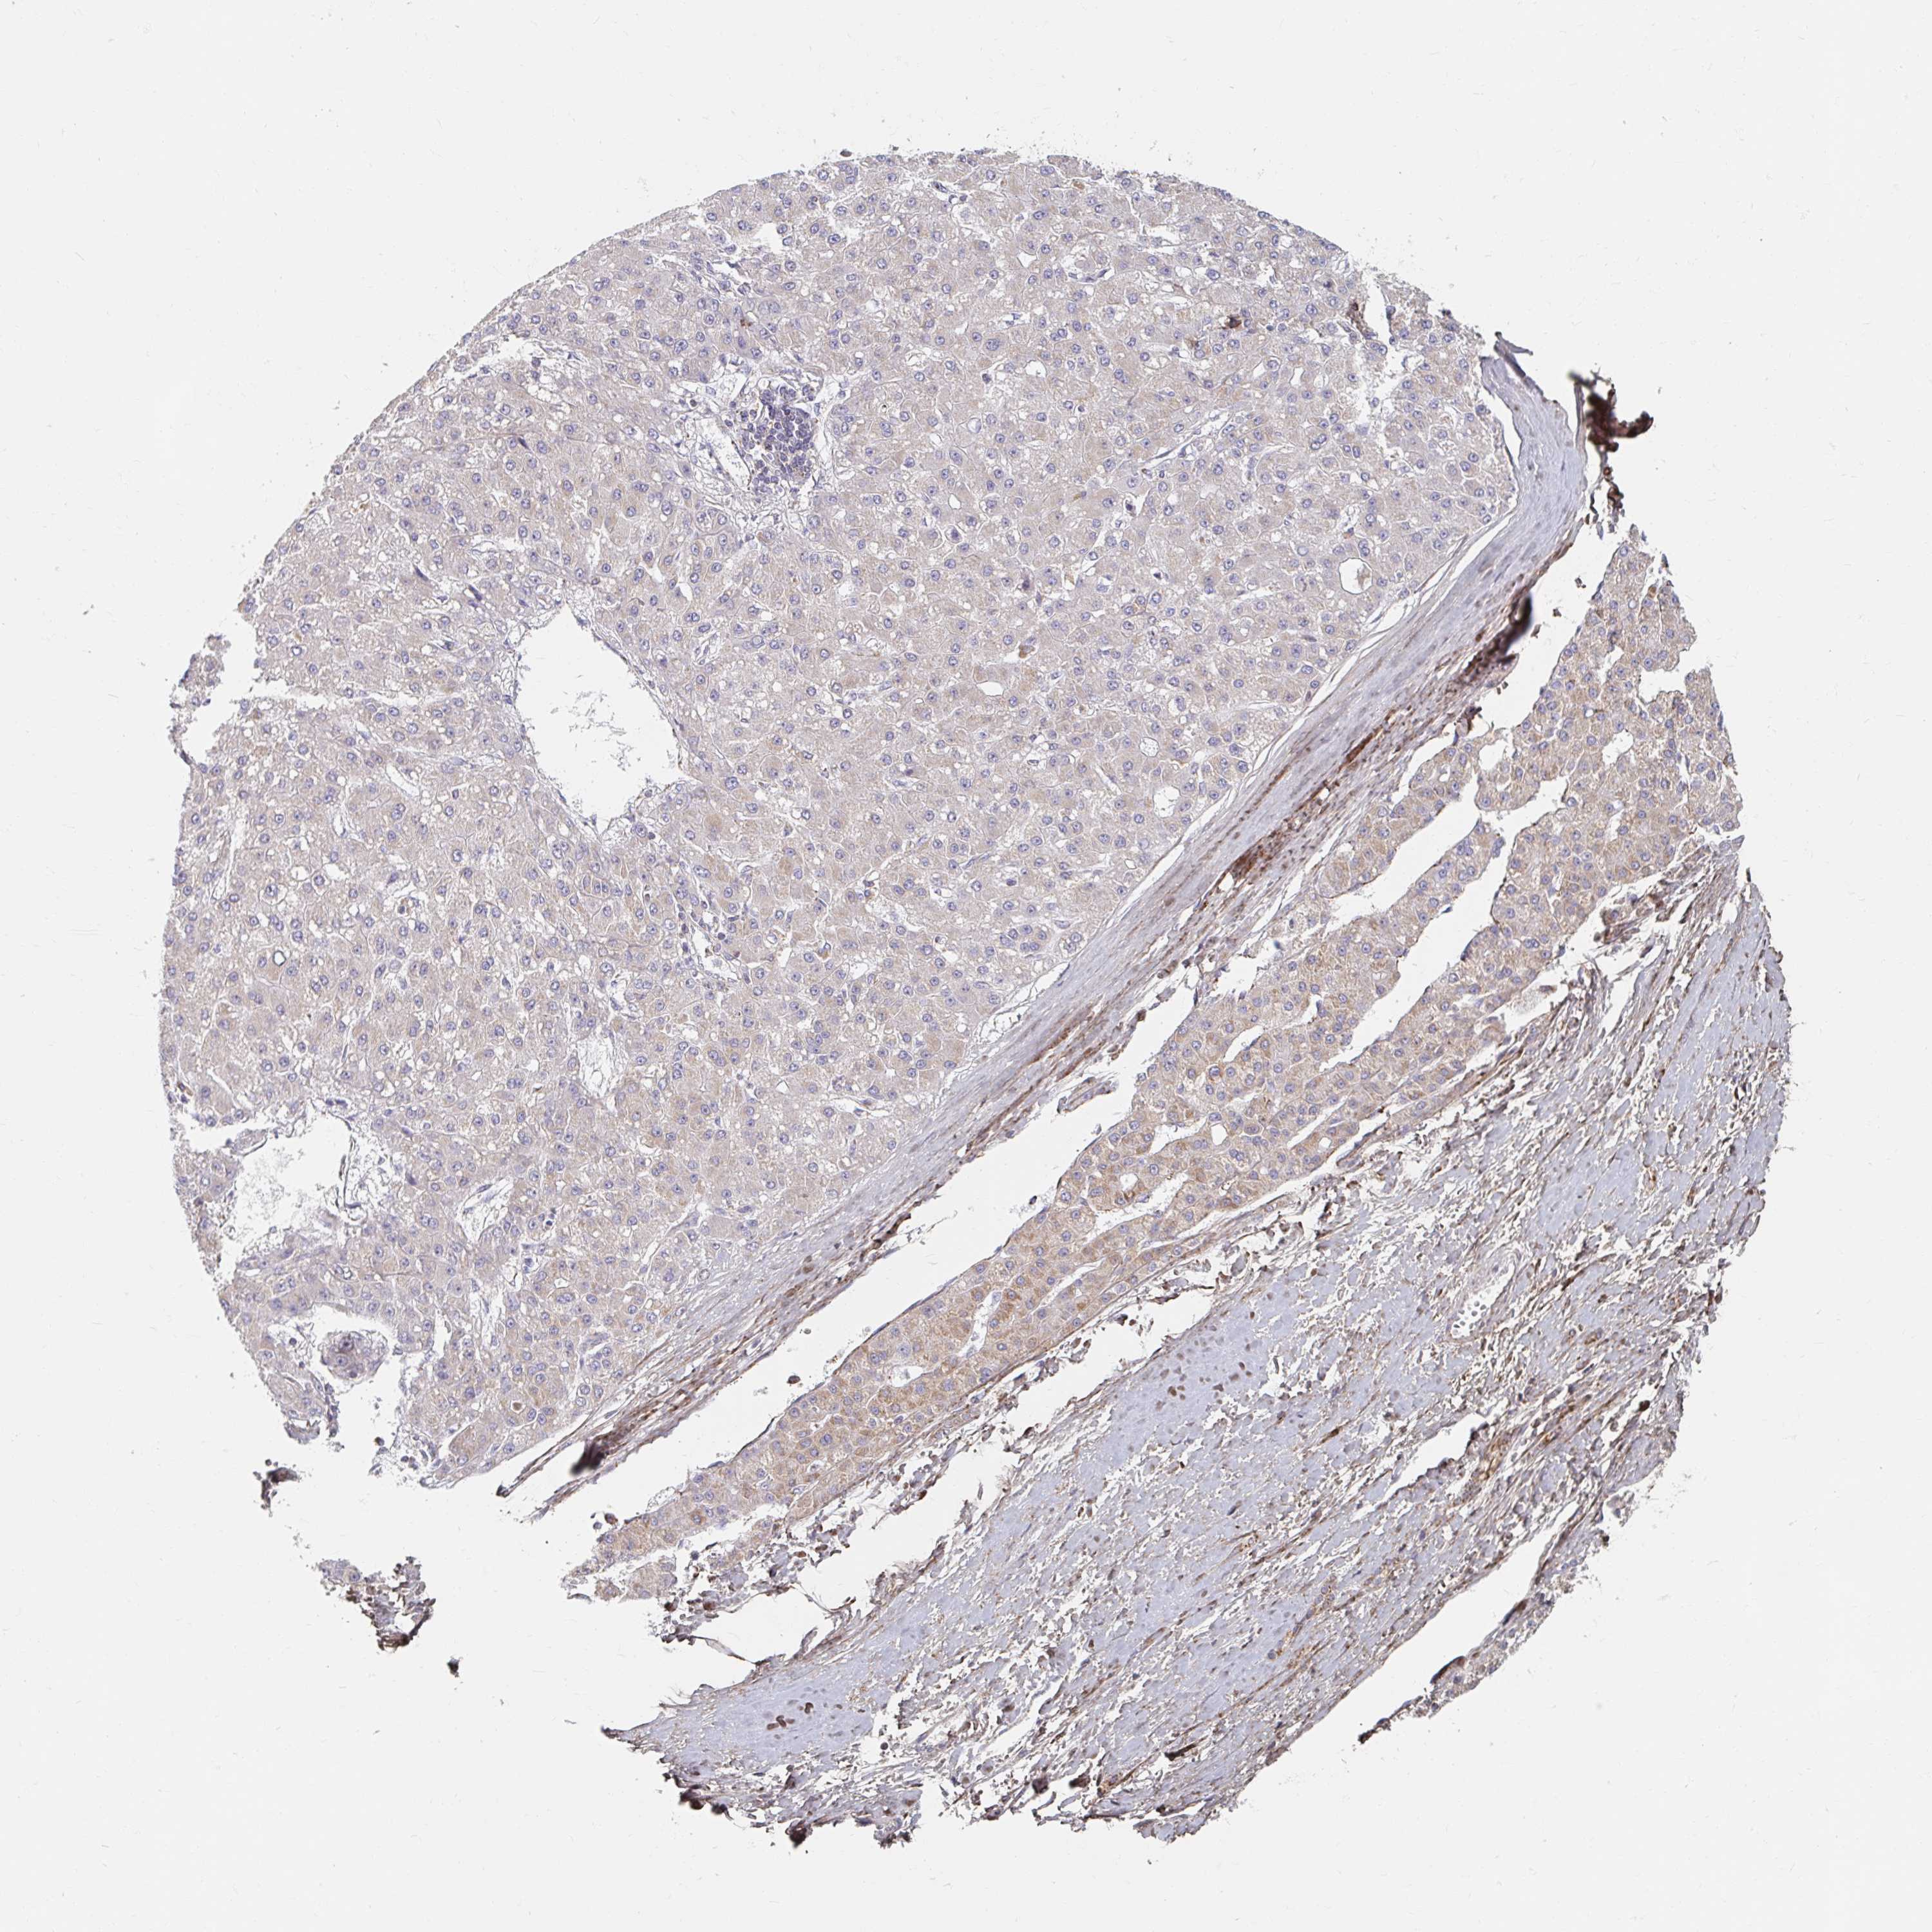

LIVER CANCER - Protein expressioni

A mouse-over function shows sample information and annotation data. Click on an image to view it in a full screen mode. Samples can be filtered based on level of antibody staining by selecting one or several of the following categories: high, medium, low and not detected. The assay and annotation is described here.

Note that samples used for immunohistochemistry by the Human Protein Atlas do not correspond to samples in the TCGA dataset.

Antibody stainingi

Antibody staining in the annotated cell types in the current human tissue is reported as not detected, low, medium, or high, based on conventional immunohistochemistry profiling in selected tissues. This score is based on the combination of the staining intensity and fraction of stained cells.

Each image is clickable and will lead to virtual microscopy that enables deeper exploration of all samples and also displays staining intensity scores, fraction scores and subcellular localization as well as patient and tissue information for each sample.

Antibody HPA049850

Antibody HPA053524

Antibody CAB009187

Staining

High

Medium

Low

Not detected

Intensity

Strong

Moderate

Weak

Negative

Quantity

>75%

75%-25%

<25%

None

Location

Nuclear

Cytoplasmic/membranous

Cytoplasmic/membranous,nuclear

Carcinoma, Hepatocellular, NOS